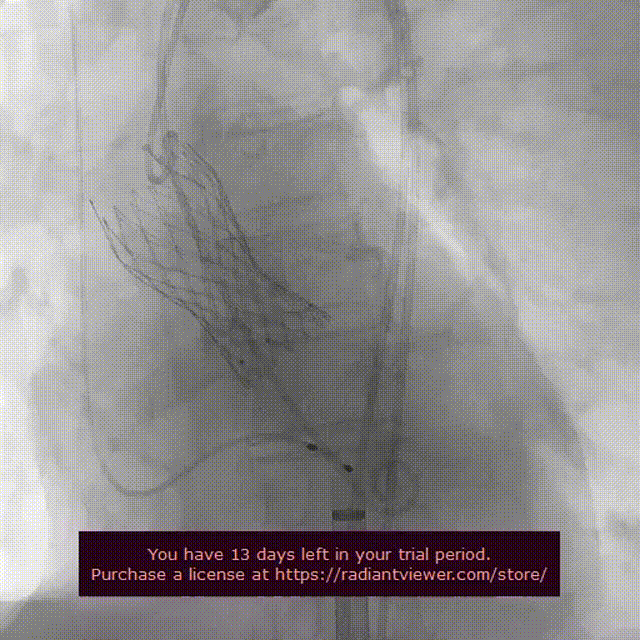

左冠病变

左冠修复后